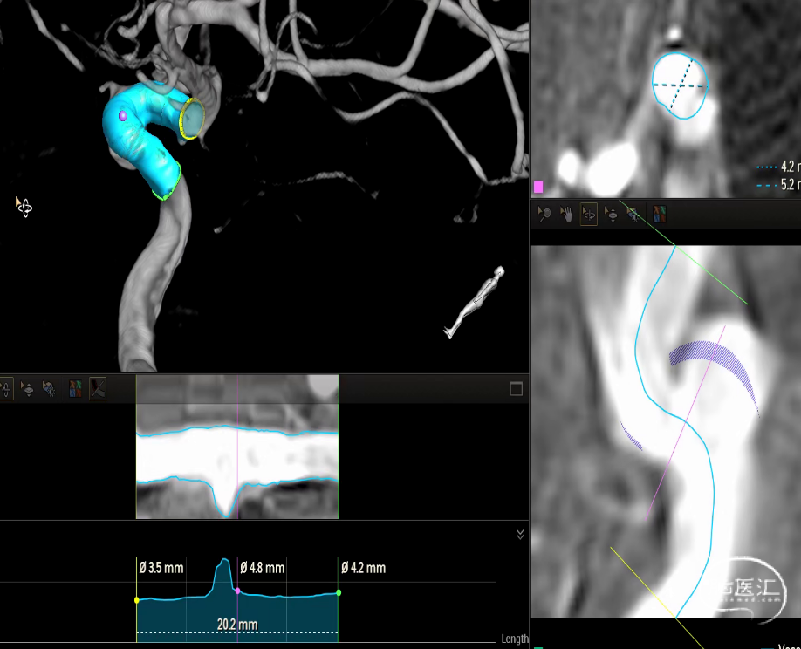

术前检查

DSA:双侧眼段动脉瘤

•DSA手术规划:选择麒麟血流导向装置4.0x20